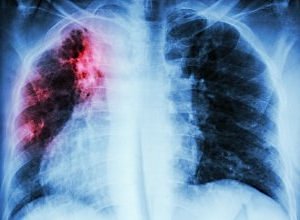

Rates of tuberculosis (TB) recurrence increased by almost nine-fold between episode 2 and 5 regardless of HIV status, according to a study assessing recurrent tuberculosis in Cape Town, South Africa, over a 13-year period.

Hermans and colleagues at Desmond Tutu HIV Centre, Institute for Infectious Disease and Molecular Medicine, University of Cape Town determined the rate of recurrent TB per subsequent episode by matching individual treatment episodes in Cape Town which has one of the highest TB burdens worldwide between 2003 and 2016. The researchers then estimated the recurrence rate, stratified according to subsequent TB episode and HIV status, among patients with a first episode of TB who finished treatment successfully, adjusting person-time to background mortality according to age, sex and HIV status.

A total of 292,915 TB episodes among 263,848 individuals were included in the study. Results showed that the rate of recurrent TB was 16.4 per 1,000 person-years (95% CI, 16.2-16.6) and increased per subsequent episode by 8.4-fold, from 14.6 to 122.7 per 1,000 from episode 2 to episode 6, respectively. The researchers observed similar increases when results were stratified according to HIV status. Rates among people living with HIV were higher than those of individuals without HIV for episodes 2 and 3 (2 and 1.5-fold higher, respectively) and the same thereafter.

“We found a high rate of TB disease recurrence increasing per subsequent episode, which was independent of previous treatment outcome and HIV status. These findings suggest the HIV epidemic cannot fully explain the high burden of retreatment TB in Cape Town,” the authors wrote. “Therefore … high ART coverage will not be sufficient to curb it.”

Instead, Hermans and colleagues say that the burden “is more likely explained” by high transmission rates as well as an increased risk for infection or progression to disease associated with prior TB treatment. They also call for further research into the mechanisms underlying this correlation.

“The very high recurrence rates would justify increased TB surveillance of patients with more than one episode,” the researchers wrote.